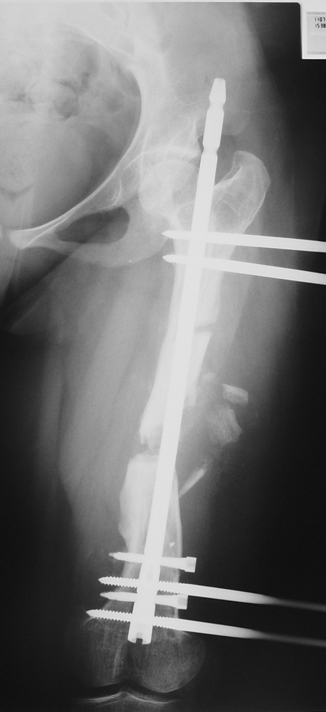

3. POSTTRAUMATIC LOWER LIMB SHORTNESS (MALUNION)

This type of shortness occurs after a fracture heals in a shortened position. Most cases are seen in adults and can be treated with one lengthening operation. Additional deformities can be corrected simultaneously. Most of these cases can be treated with lengthening over nail or just corrections and intramedullary nailing.